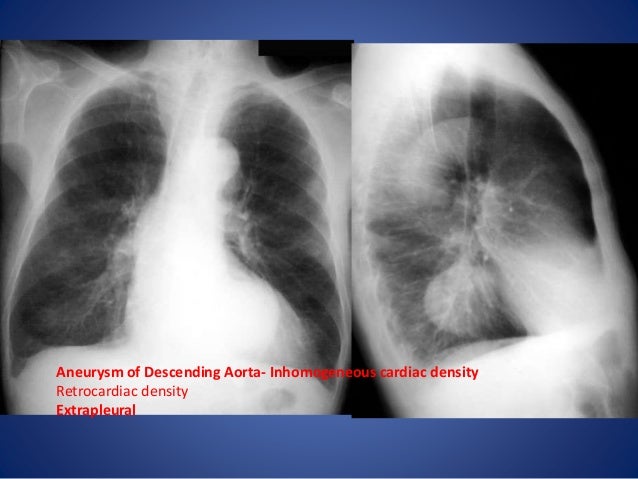

By early detection and proper evaluation of the abnormal retrocardiac shadows the radiologist may establish the diagnosis before the clinical signs and symptoms of compression of large blood vessels and nerves become. Retrocardiac Air Space Disease. Air space opacification is a descriptive term that refers to filling of the pulmonary tree with material that attenuates x-rays more than the surrounding lung parenchyma.

Airspace disease is considered chronic when it persists beyond 4-6 weeks after treatment. A single retrocardiac air-fluid level on a chest radiograph typically implies the presence of a sliding hiatal hernia. This unusual type of bibasilar atelectasis happens when the lung is trapped as a result of pleural disease while being devoid of air. Airspace disease also known as alveolar lung disease is a generic term thats used to describe abnormalities on chest x-ray or CT. The most common clinical causes of this CT pattern of disease include hypersensitivity pneumonitis sarcoidosis atypical infections eg those caused by Mycoplasma pneumoniae with associated bronchiolitis and acute interstitial pneumonia 25. The 2021 edition of ICD-10-CM J984 became effective on October 1 2020. J984 is a billablespecific ICD-10-CM code that can be used to indicate a diagnosis for reimbursement purposes. And retrocardiac air space disease. Retrocardiac Air Space Disease.

The location retrocardiac - behind the heart shouldnt make a difference. It is the radiological correlate of the pathological diagnosis of pulmonary consolidation. The most common clinical causes of this CT pattern of disease include hypersensitivity pneumonitis sarcoidosis atypical infections eg those caused by Mycoplasma pneumoniae with associated bronchiolitis and acute interstitial pneumonia 25. The particular way the lung collapses can often produce a. Acinar or air-space nodules. CT 5-mm slice thickness in a patient with bilateral consolidation. Tendency to coalesce near hila.